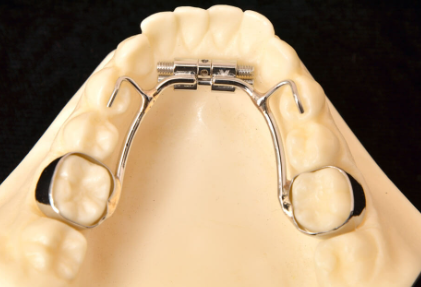

For upper expansion, he prefers using a Quad Helix appliance.

The Quad Helix is smaller and less bulky than older traditional expanders, making it more comfortable and easier for children to keep clean. One of its greatest advantages is that it does not require parents to perform daily turning at home. Dr. Freeman makes precise adjustments during visits, allowing for controlled and customized expansion without placing additional stress on families.